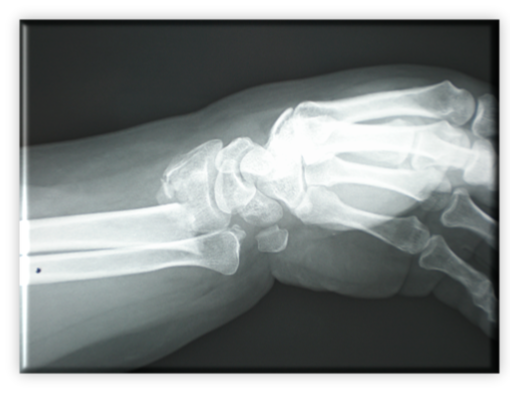

Πολύ σύνηθες κάταγμα συνεπεία πτώσεως και στήριξης στο χέρι με τον καρπό σε έκταση. Η συχνότητα είναι μεγαλύτερη σε μετεμμηνοπαυσιακές γυναίκες με οστεοπόρωση. Συμβαίνει βέβαια και σε νεότερα υγειά άτομα, όπως και σε παιδιά, αλλά απαιτείται μεγαλύτερη βία.

Οι ανωτέρω ακτινογραφίες αναδεικνύουν ένα τέτοιο κάταγμα, σε πλήρη παρεκτόπιση χωρίς επέκταση στην αρθρική επιφάνεια. Το κάταγμα αυτό περιγράφηκε για πρώτη φορά από τον Ιρλανδό ιατρό Colles πριν την ανακάλυψη και χρήση των ακτινογραφιών. Φέρει τιμητικά το όνομά του.

Αρχικά αντιμετωπίστηκε με κλειστή ανάταξη και γύψωση, υπό τοπική αναισθησία, στο θάλαμο επειγόντων.

Πρόκειται όμως για ασταθή κατάγματα και παρά την ικανοποιητική ανάταξη και γύψωση, μερικές φορές το κάταγμα παρεκτοπίζεται στο γύψο. Η τελική αντιμετώπιση ήταν η σταθεροποίηση με βελόνες Κirschner, μια ανέξοδη και πολύ αποτελεσματική μέθοδος. Ο συνολικός χρόνος ακινητοποίησης είναι 6 εβδομάδες και συνήθως ακολουθεί περίοδος φυσικοθεραπείας. Μετά από ένα τέτοιο κάταγμα σε μια μετεμμηνοπαυσιακή γυναίκα, εξέχουσας σημασίας είναι ο έλεγχος και θεραπεία οστεοπόρωσης.